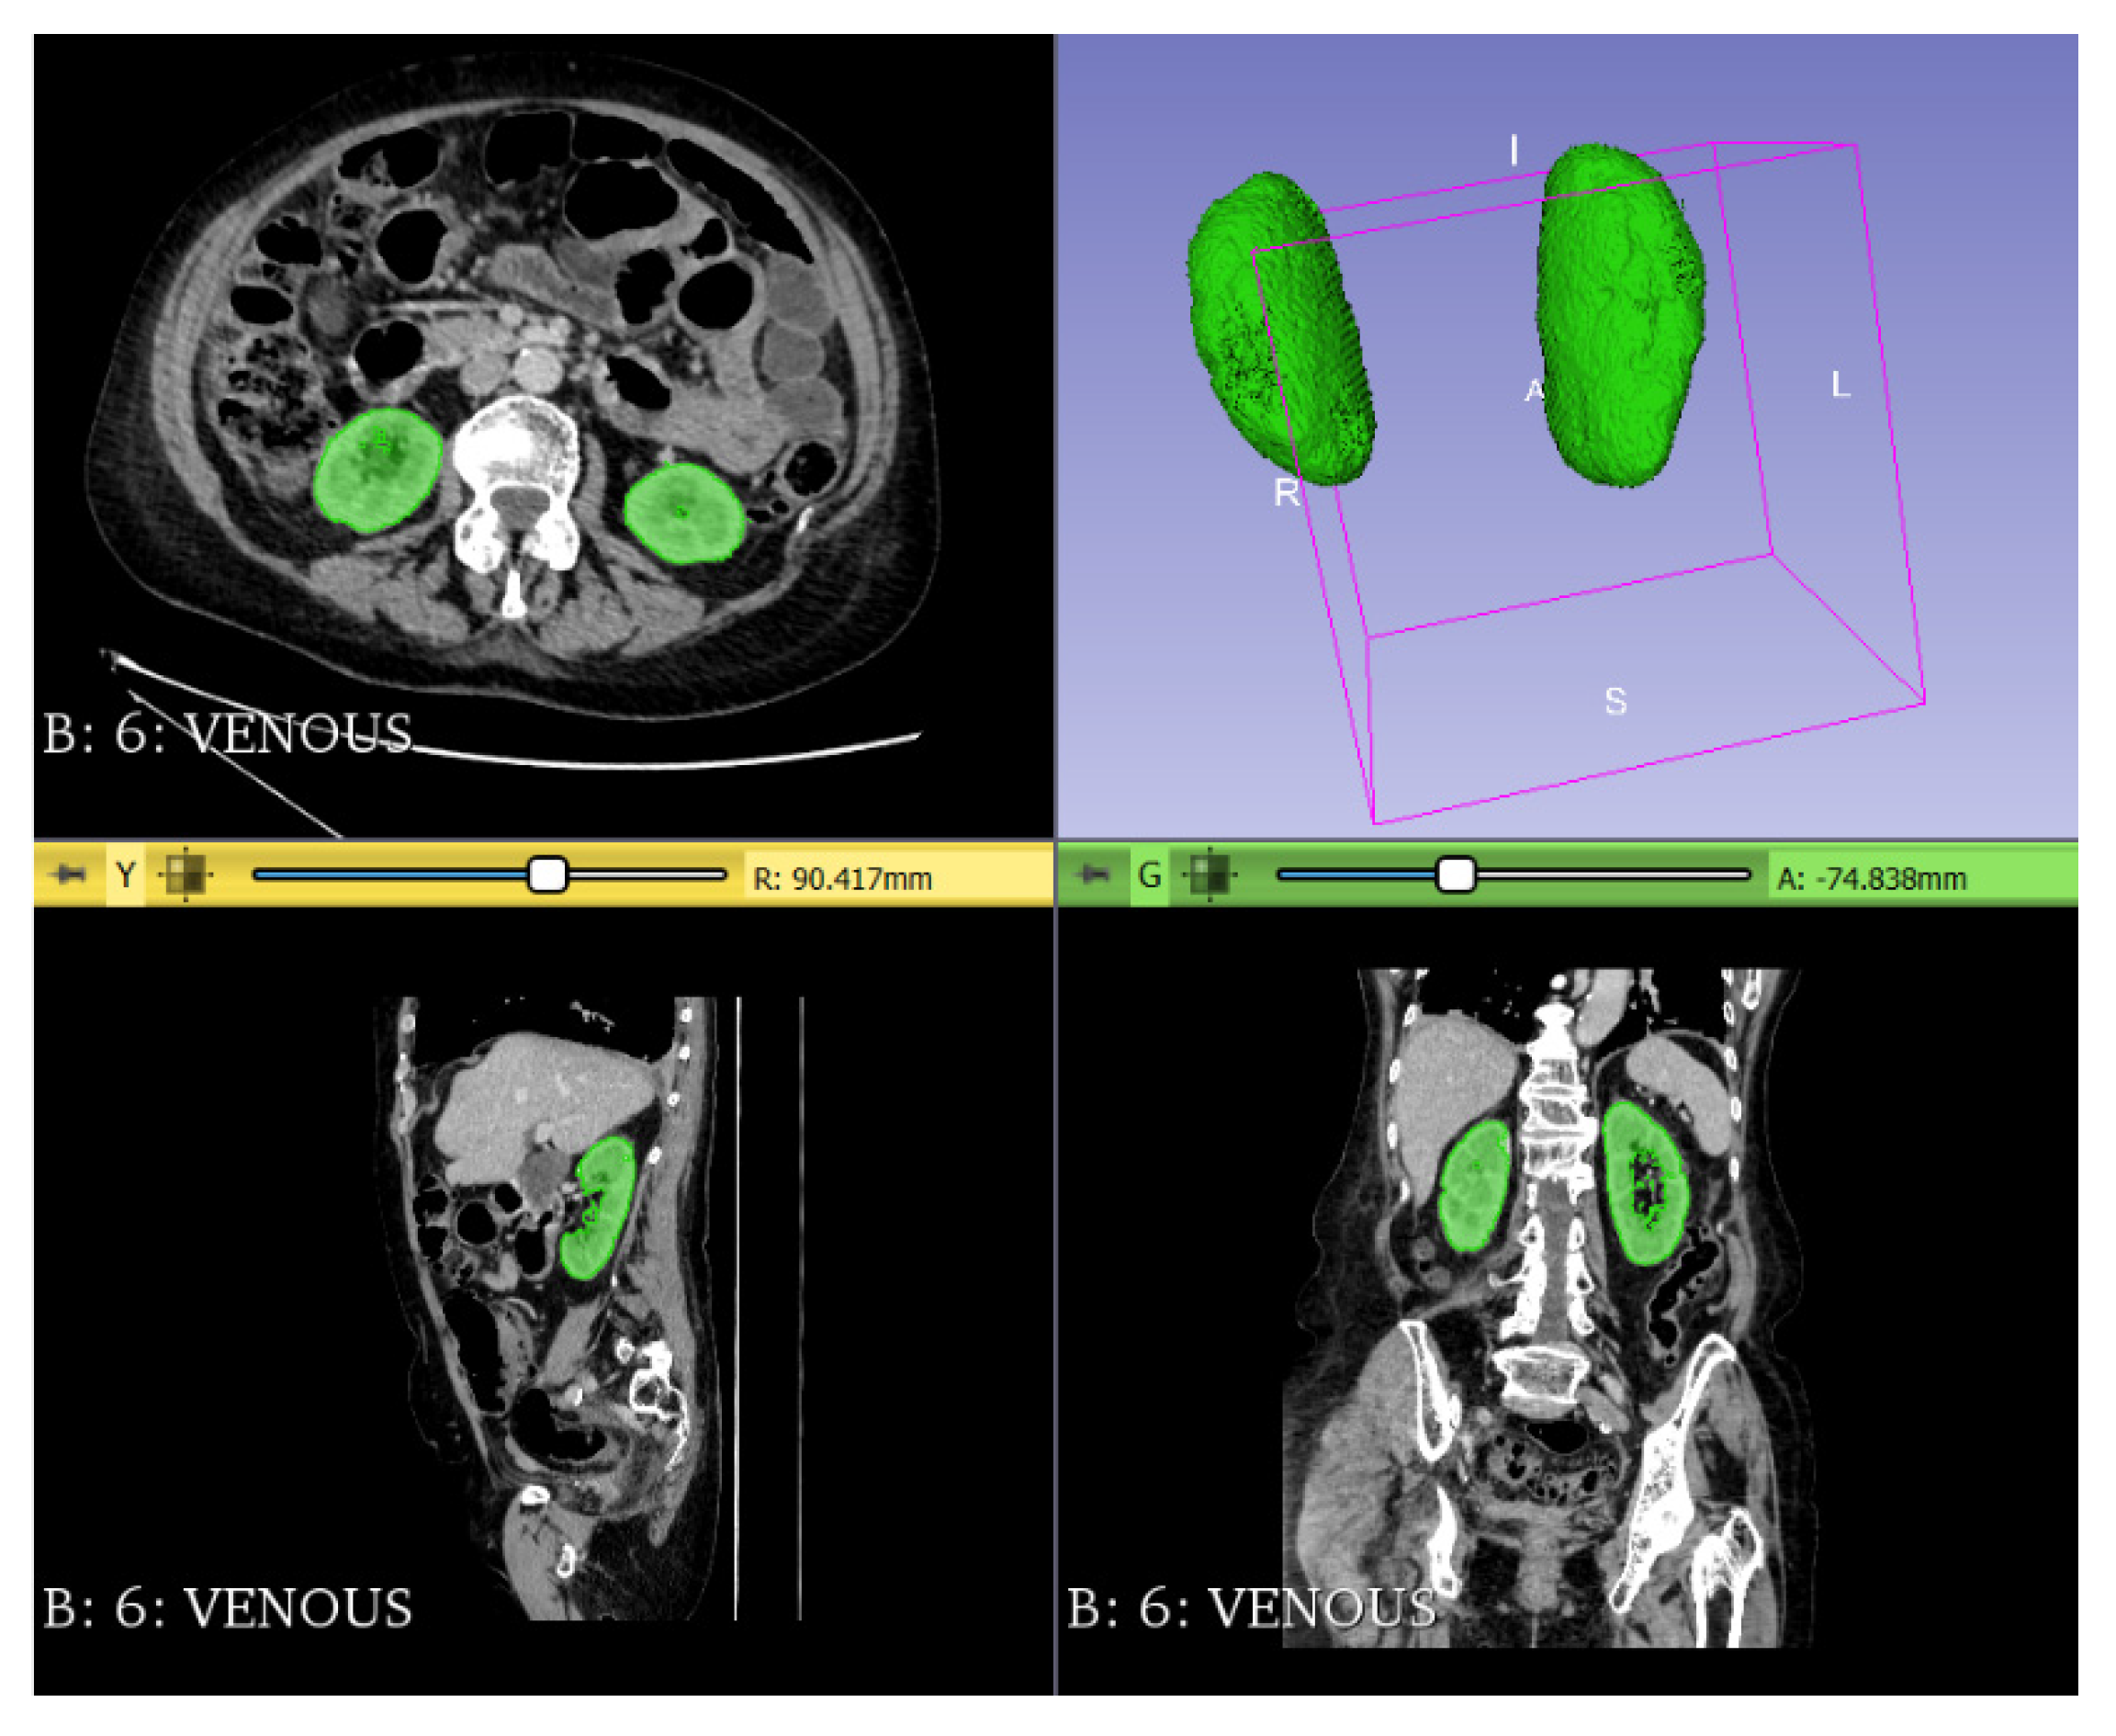

| Median psoas muscle area/height (IQR) (cm2/m) | 7.16 (5.01–9.41) | 7.61 (5.38–9.70) | 5.19 (4.06–7.39) | <0.001 |

| Number of patients with psoas area/height under cut-off point | 94 (36.0%) | 65 (30.2%) | 29 (63.0%) | <0.001 |